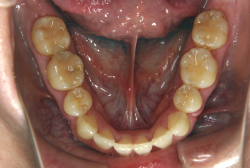

凸凹な歯並びのことを叢生といいます。矯正歯科に来院する患者様の主訴の中で、最も多いのが「配列の凸凹を真っ直ぐにしたい」というものです。歯の大きさと顎の大きさの調和がとれていないことが原因です。

凸凹を主体としたケースの場合、当院の平均治療期間は18ヶ月ですので、このケースは少し長めに経過しました。理由の一つは凸凹の程度がかなり重症だったと言うことですが、もう一つは、右下第2大臼歯が45度くらい前傾していたため、それを整直化させるために時間を要したと考えています。いずれにしても最終結果は大変よい状態と思います。

治療前は並びが乱れて見た目が悪いというのはもちろん問題ですが、歯科医学的に一番困るのは噛み合わせが悪いという点です。上下の犬歯(3番目の歯)は、上下的に離れた位置にあるため接触することができません。つまり歯としては存在していても、歯としては機能していないということです。